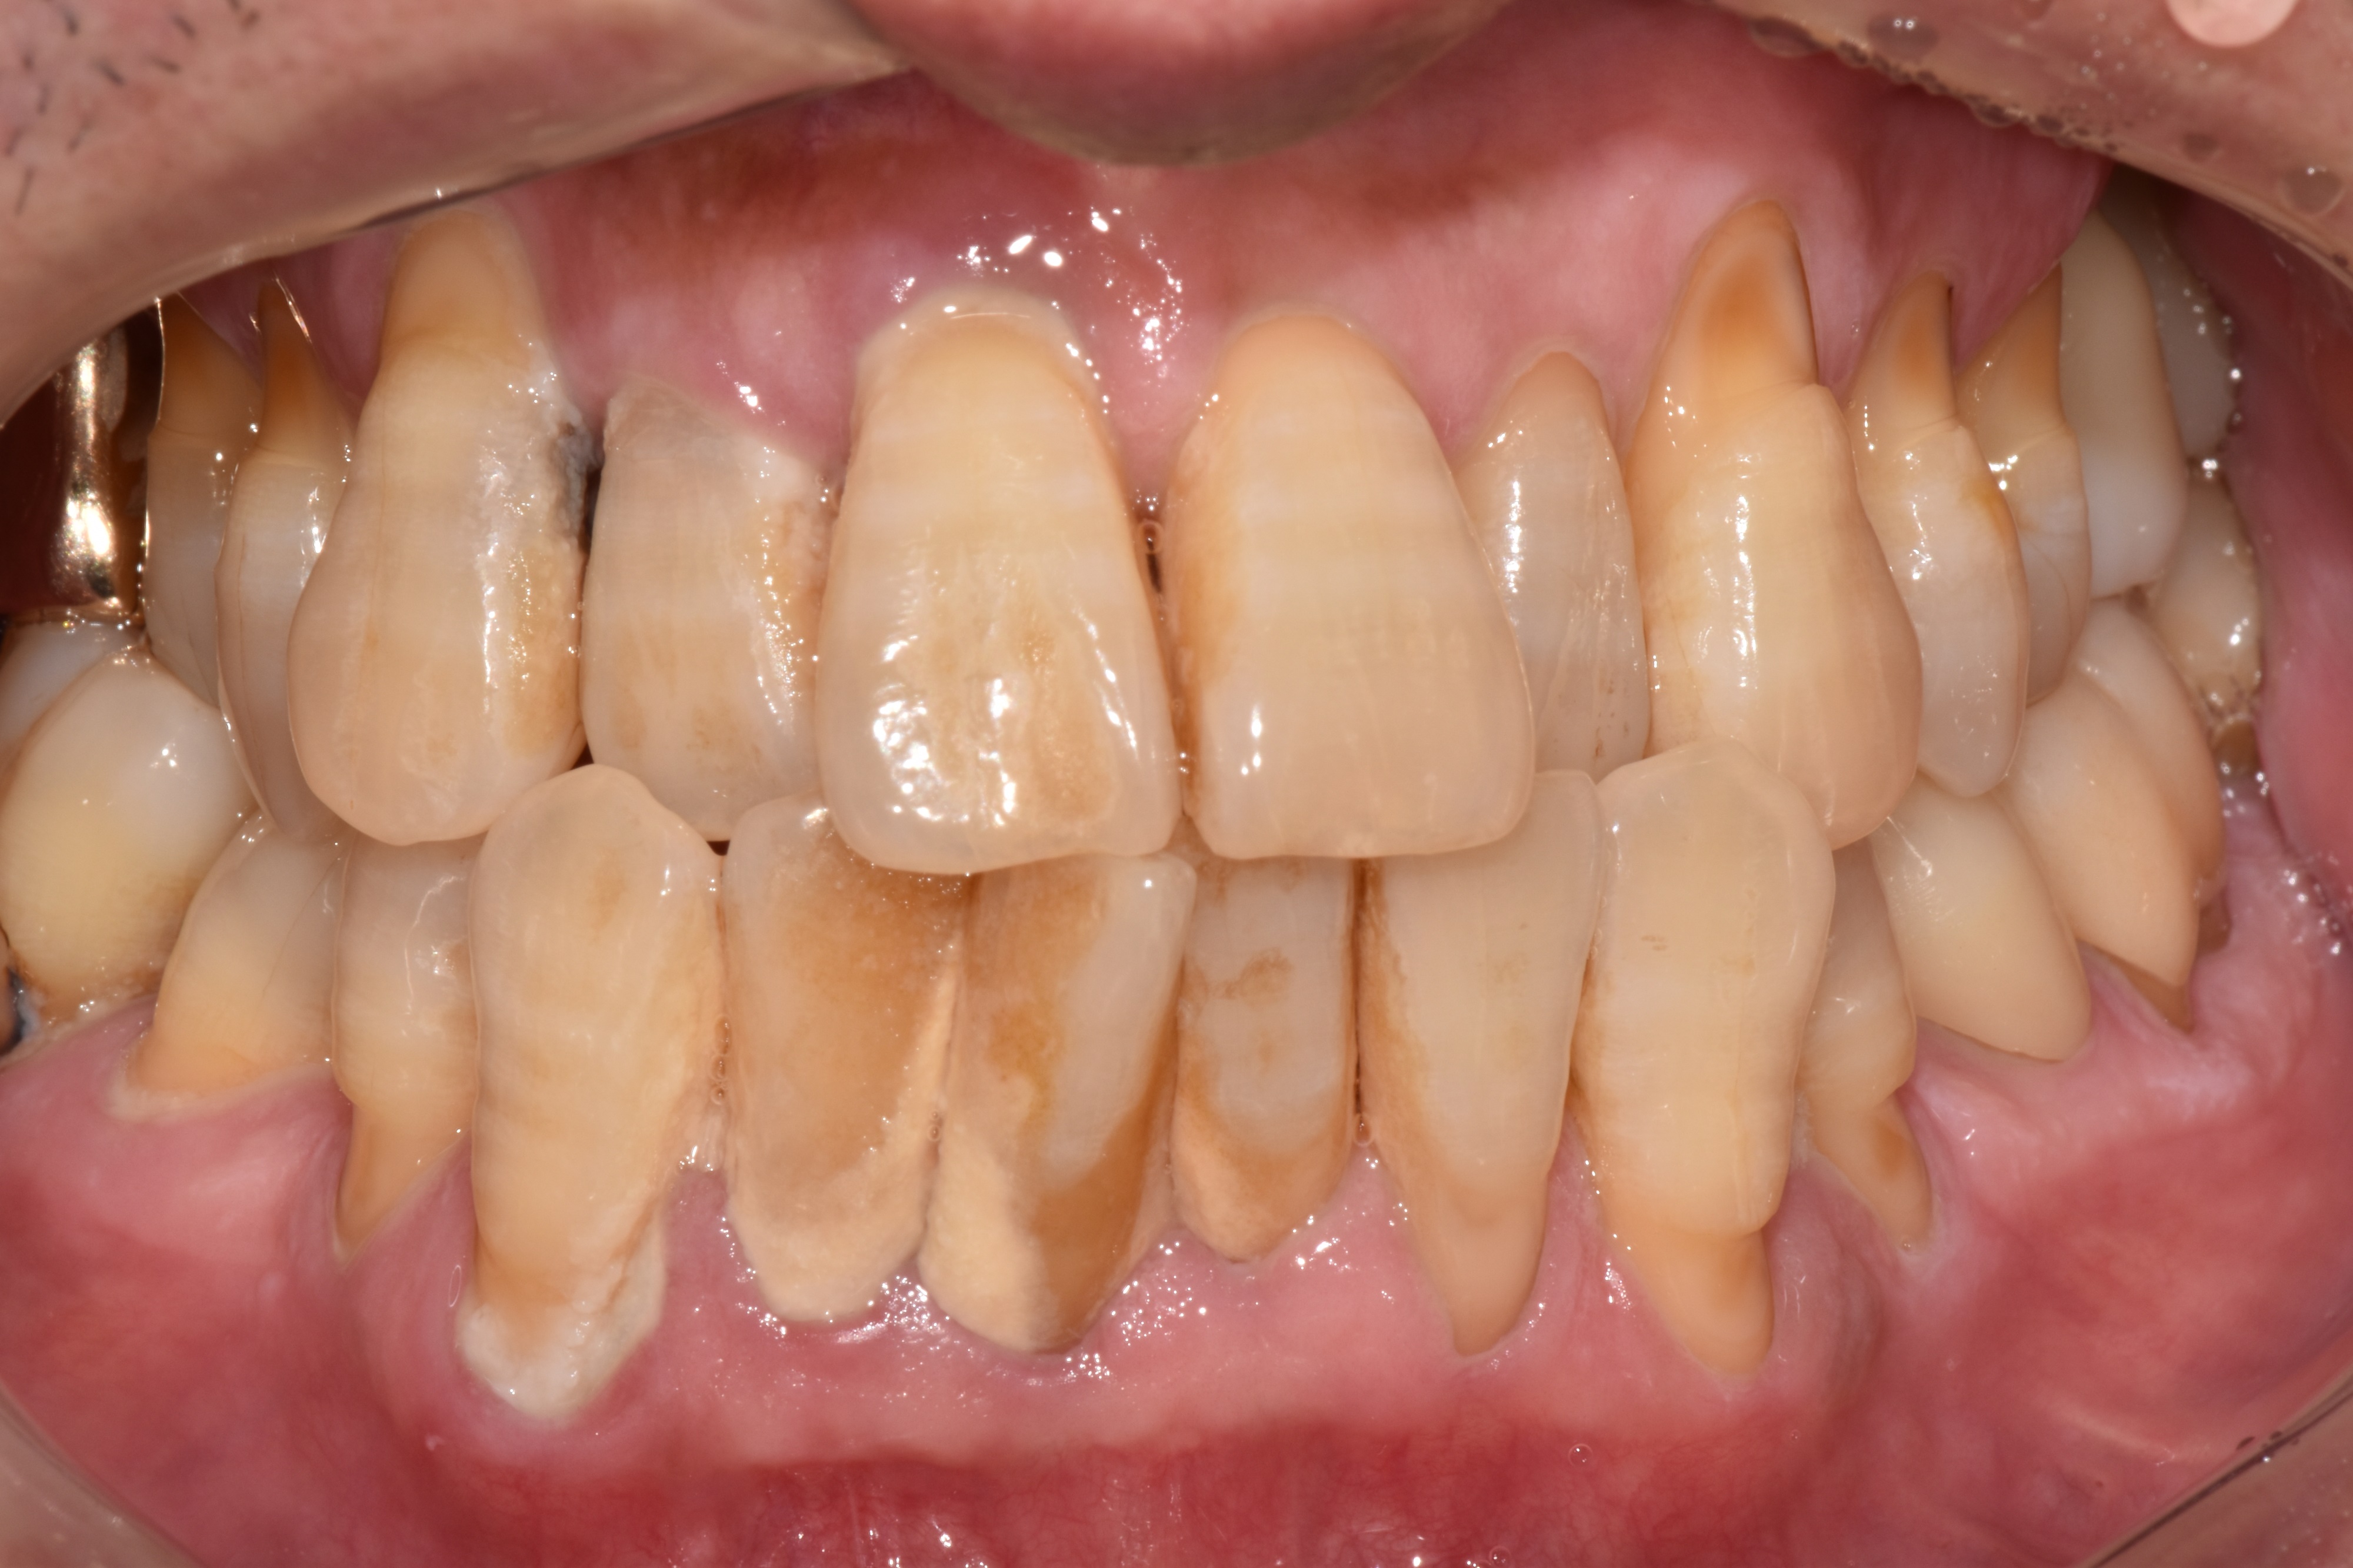

"정기적인 관리 덕분에

50대에도 모든 치아가 건강해요"

Before

After

치석과 잇몸 염증이 심했던 상태

정기적인 스케일링과 관리로 건강하게 유지